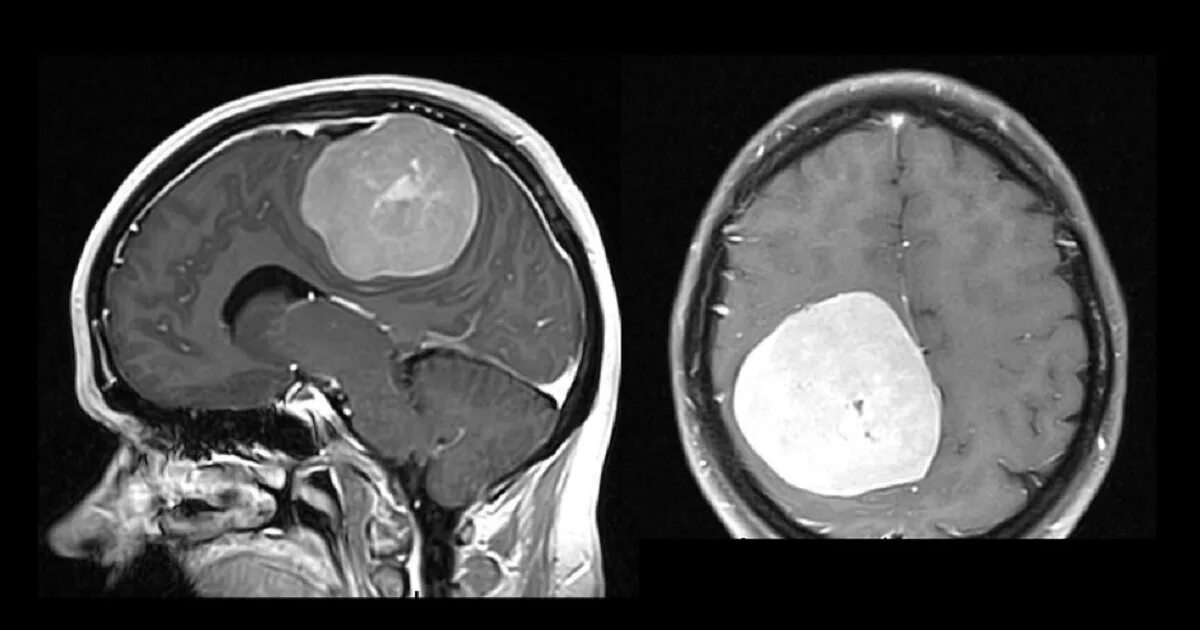

Сколько живут с доброкачественной опухолью головного мозга